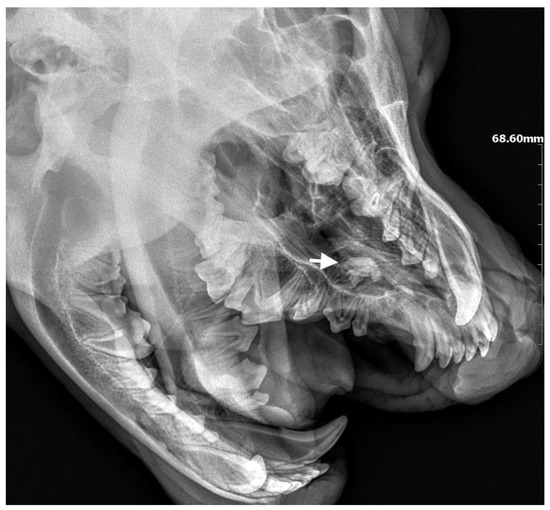

A 3-year-old German Shepherd dog was referred with a suspected periapical abscess of a tooth on the right side. The medical history of the pet client reported that the dog had been treated for chronic rhinitis for 6 months. On clinical examination, tooth 104 (right maxillary fang) was observed to be missing, with no wounds or fistulas in the oral cavity. Rhinoscopic examination showed features of chronic rhinosinusitis, with convexity of the nasal wall mucosa on the right side of the nasal cavity, without proliferative changes or foreign bodies. Radiological examination revealed the presence of an ectopic tooth located outside the alveolar process in the region of the maxillary cranium. Its shape was not characteristic of any normal tooth. It had a soppy crown and an incompletely formed root. The tooth was surrounded by a dentigerous cyst measuring 5.6 × 2.8 cm (Figure 5). After tooth extraction using the CLP technique and cyst lysing, the bone defect was filled with a hydroxyapatite polymer material previously soaked in 0.9% NaCl. The plasticity of the material was exploited so that it was possible to fill the bone defect with the material through a dissected bone window of 3 cm in diameter without enlarging the bone defect. A follow-up X-ray 28 days after the procedure showed normal filling of the defect with bone, without signs of inflammation or granulation formation within the jawbone. On clinical examination, resolution of nasal discharge problems and the absence of features of inflammation within the nasal cavity were observed (Figure 6).

Figure 6. X-ray showing the condition of the jawbone 28 days after tooth extraction. The bone defect is filled with bone tissue without signs of inflammation (marked with arrows).